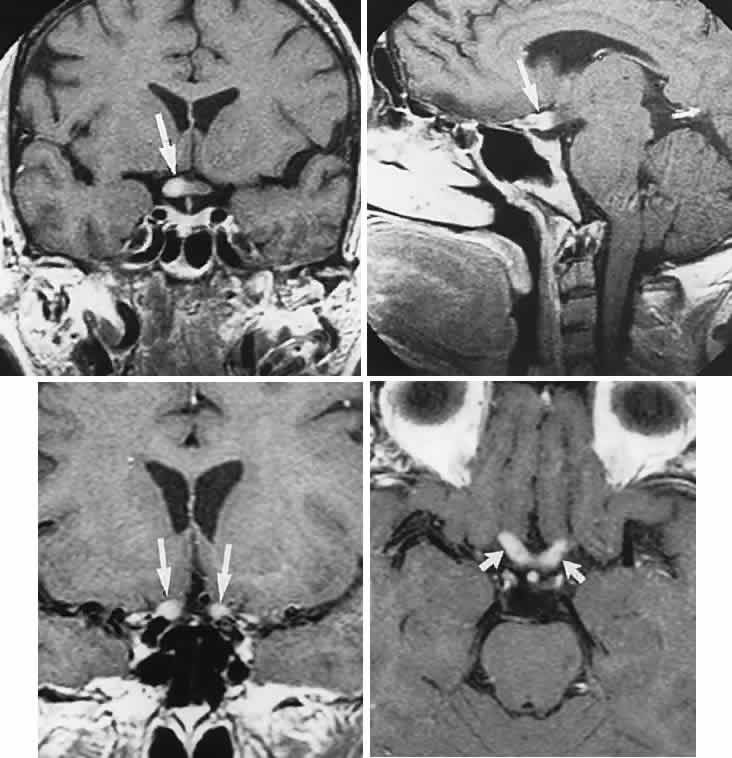

in the acute stage of Leber's hereditary optic neuropathy. J Neurol Neurosurg Psychiat 64:124, 1998 88. Nikoskelainen EK, Huoponen K, Juvonen V et al: Ophthalmologic findings in Leber hereditary optic neuropathy, with special

treated with growth hormone. J Pediatr 126: 996, 1995 173. Alexandrakis G, Filatov, Walsh T: Pseudotumor cerebri in a 12-year-old boy with Addison's disease. Am J Ophthalmol 116:650, 1993 174. Liu GT, Kay MD, Bienfang DC et al: Pseudotumor cerebri associated with corticosteroid withdrawal in inflammatory